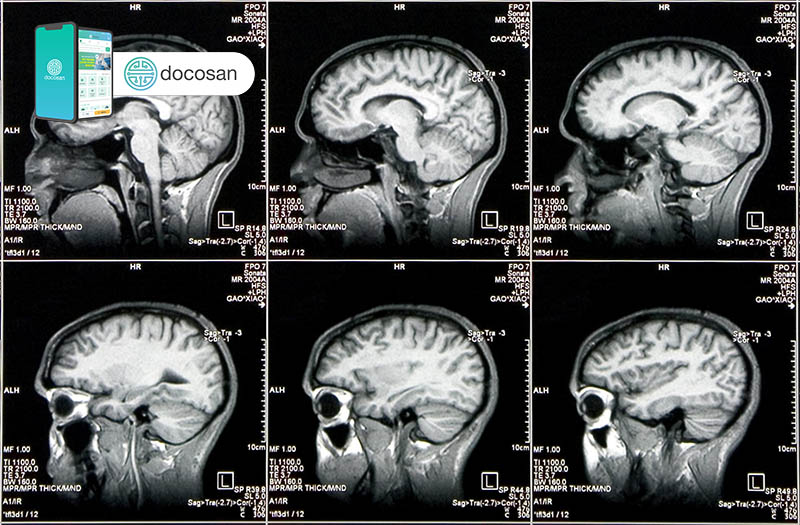

Chụp cắt lớp não cho thấy một số bệnh nhân mắc chứng hưng cảm có cấu trúc hoặc hoạt động của não hơi khác so với người bình thường. Chẳng hạn như những người thiếu hụt lượng tế bào đệm thần kinh hoặc khiếm khuyết về cấu trúc tế bào thần kinh, đặc biệt vùng vỏ trán, sẽ có nguy cơ bị hưng cảm nhiều hơn.